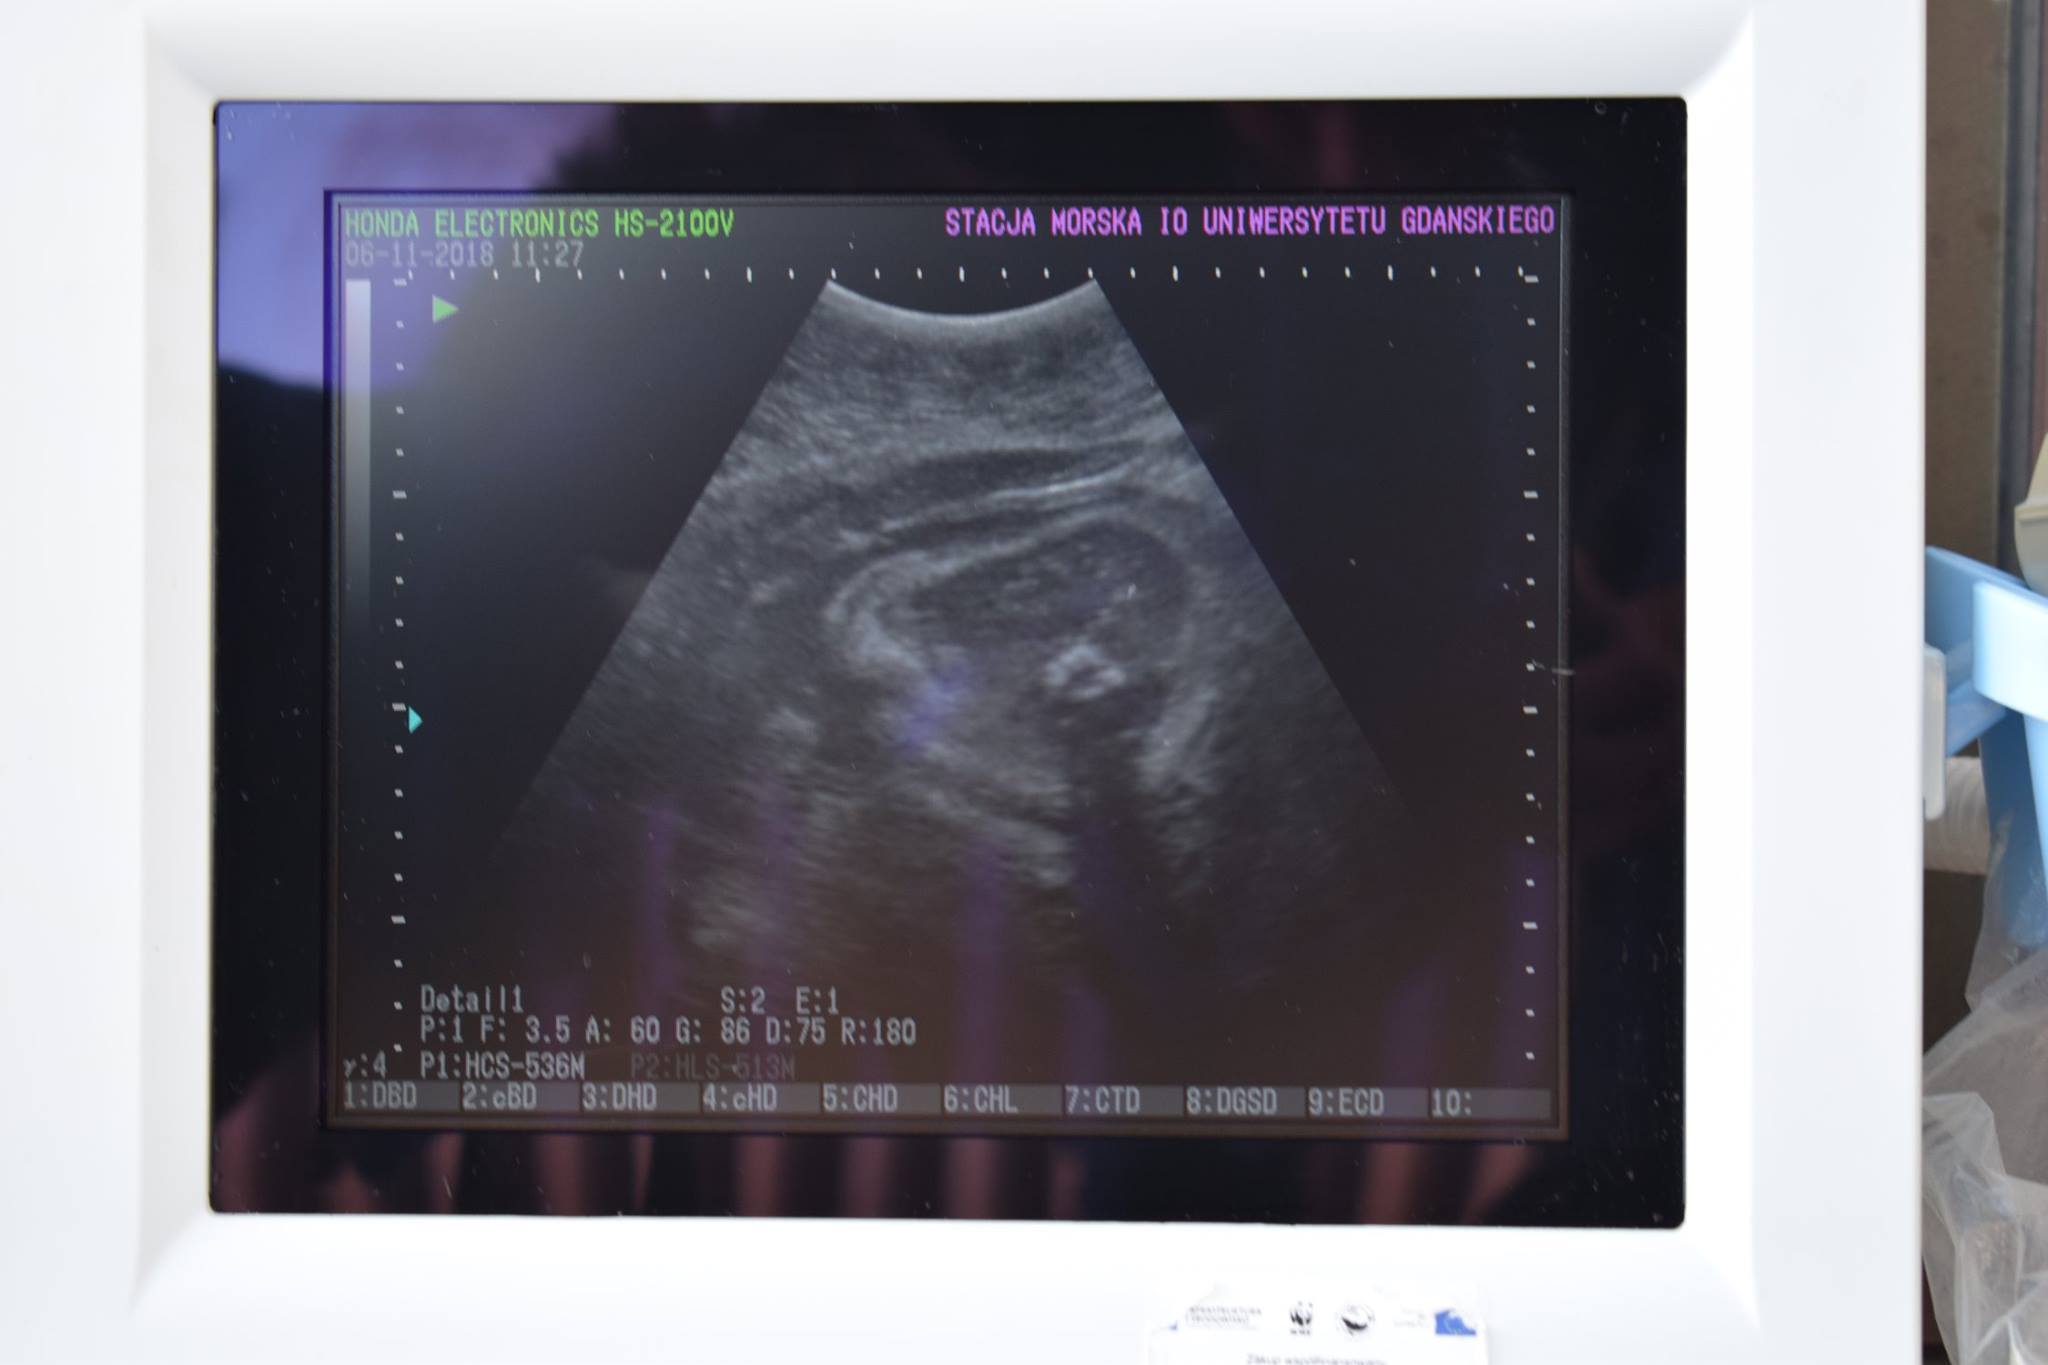

Ekran monitora USG ukazał zarys rozwijających się focząt – trzy helskie foki są w ciąży. Dobrą nowinę ogłosiło fokarium w Helu. Samice są zdrowe, a ich potomkowie mają przyjść na świat na przełomie lutego i marca przyszłego roku.

Stwierdziliśmy ostatnio rosnący apetyt u naszych samic. Mogło to wskazywać, że focze damy spodziewają się potomstwa. Przeprowadziliśmy badania USG i wtedy nasze przeczucia potwierdziły się. Przyszłe mamy będą teraz szczególnie doglądane i mamy nadzieję, że wszystkie ciąże przebiegną bezproblemowo – czytamy na Facebooku fokarium.